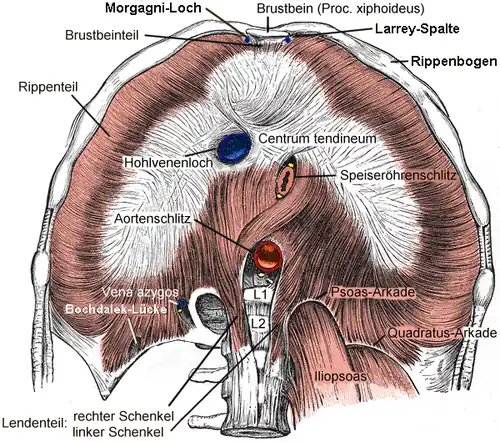

Der muskulöse Anteil des Zwerchfells wird nach dem Ursprung in drei Anteile untergliedert: Lenden-, Brustbein- und Rippenteil. Alle drei Anteile enden in einer gemeinsamen Sehnenplatte ('Centrum tendineum'), die aus den miteinander verflochtenen Sehnenfasern besteht. Das Verhältnis zwischen dem muskulösen und dem sehnigen Anteil ist innerhalb der Säugetiere variabel. Hunde und Katzen besitzen eine kleine, schmale und Y-förmige Sehnenplatte, bei den übrigen Haustieren und beim Menschen ist sie V- bis herzförmig und stellt die größte Zwerchfellportion dar. Der muskulöse Anteil des Zwerchfells wird beim Schlachttier auch Kronenfleisch genannt.

Der Lendenteil (Pars lumbalis) entspringt an der, der Bauchseite zugewandten Fläche (=ventral) der Lendenwirbelsäule. Er besteht aus einem rechten (Crus dextrum) und einem linken Schenkel (Crus sinistrum). Diese „Zwerchfellpfeiler“ stellen Muskelstränge dar, die beim Menschen nach oben (kopfwärts), bei den Tieren infolge der horizontalen Körperorientierung nach vorn (kopfwärts) ziehen. Der rechte Schenkel ist kräftiger und kann in zwei (Mensch: Crus mediale und Crus laterale) oder drei Unterabschnitte unterteilt werden. Am Lendenteil gibt es drei sehnige Bögen. Die Quadratus- (Ligamentum arcuatum laterale) und die Psoasarkade (Ligamentum arcuatum mediale) umgreifen bauchseitig die beiden Anteile des Musculus iliopsoas, die Aortenarkade (Ligamentum arcuatum medianum) den Aortenschlitz (s. u.).

(römische Ziffern = Rippennummern)

Der Rippenteil grenzt bauchseitig an den kleinen Brustbeinteil (Pars sternalis). Er entspringt am Ende des Brustbeins (Sternum), am sogenannten Schwertfortsatz (Processus xiphoideus).

Im Zwerchfell gibt es drei größere Öffnungen. Der Aortenschlitz (Hiatus aorticus) befindet sich rückenseitig zwischen den beiden Schenkeln des Lendenteils. Er ist schräg angeordnet und reicht beim Menschen vom ersten Lendenwirbel bis zum elften Brustwirbel. Durch den Aortenschlitz ziehen die Hauptschlagader (Aorta) und ein großer Lymphsammelstamm, der Ductus thoracicus. Der Speiseröhrenschlitz (Hiatus oesophageus) liegt zwischen den Unterabschnitten des rechten Lendenschenkels, beim Menschen in Höhe des zehnten Brustwirbels. Durch den Speiseröhrenschlitz ziehen die Speiseröhre (Oesophagus) sowie die beiden Hauptstämme des Nervus vagus (Truncus vagalis anterior und posterior, bei Tieren als Truncus vagalis ventralis und dorsalis bezeichnet). Die dritte größere Öffnung ist das Hohlvenenloch (Foramen venae cavae). Es befindet sich in der Sehnenplatte. Durch dieses Loch zieht die untere Hohlvene (Vena cava inferior, bei Tieren Vena cava caudalis). Im Gegensatz zu den beiden Schlitzen, in denen die durchtretenden Strukturen verschiebbar gelagert sind, ist die Hohlvene in einem festen Bindegewebsring mit dem Zwerchfell verwachsen. Diese Verwachsung ist für die Formveränderung des Zwerchfells bei der Kontraktion verantwortlich und verhindert das Zusammenfallen der Vene.

Darüber hinaus gibt es einige kleinere Öffnungen. Im rechten Lendenschenkel befindet sich eine Öffnung für die Vena azygos und den Nervus splanchnicus major. Rückenseitig vom Aortenschlitz tritt der Grenzstrang (Truncus sympathicus) durch das Zwerchfell. Zwischen den muskulösen Anteilen liegen nur durch lockeres Bindegewebe verschlossene, muskelfreie Bezirke. Die Larrey-Spalte (Trigonum sternocostale sinistrum) und das Morgagni-Loch (Trigonum sternocostale dextrum) liegen links bzw. rechts zwischen Rippen- und Brustbeinteil. Durch sie zieht die Vena epigastrica superior (bei Tieren Vena epigastrica cranialis), der Endast der inneren Brustkorbvene (Vena thoracica interna). Zwischen Rippen- und Lendenteil liegt beidseitig die Bochdalek-Lücke oder das Bochdalek-Dreieck (Trigonum lumbocostale, in der Veterinäranatomie Arcus lumbocostalis). An diesen Stellen ist das Zwerchfell am schwächsten, weshalb hier am häufigsten Eiteransammlungen (Abszesse) durchbrechen oder Zwerchfellbrüche auftreten. Weitere Schwachstellen sind der Aorten- und der Speiseröhrenschlitz, da hier ebenfalls nur lockeres Bindegewebe die Öffnung stabilisiert.